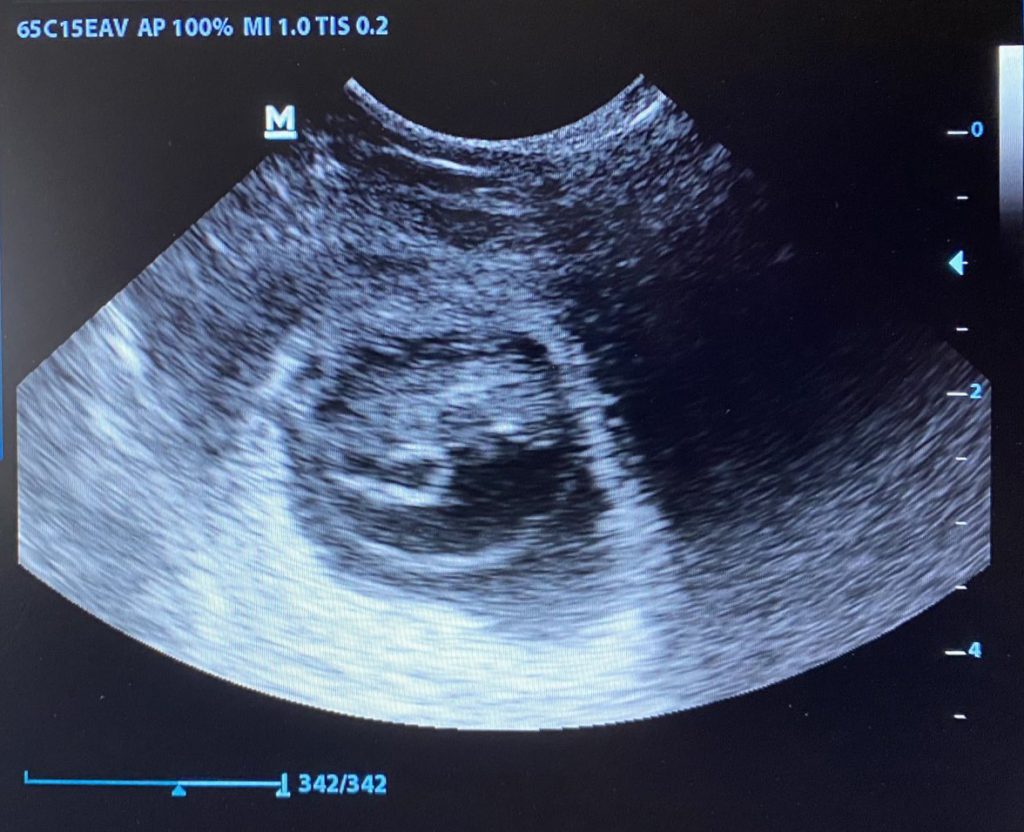

Feebee wird zunehmend unruhig – äußerlich sowie innerlich, wo wortwörtlich das Leben zu toben scheint. Unsere Prognose: morgen könnte Feebee der große Wurf gelingen!